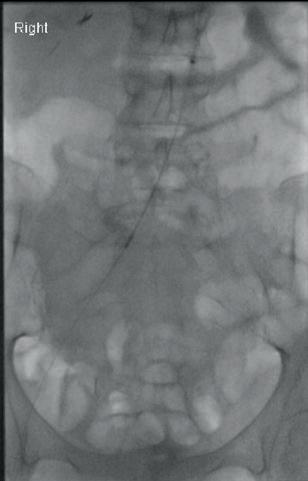

The study was a retrospective review of 66 patients with a median age of 31 who underwent UAE for uncontrolled postpartum haemorrhage at a single, high-volume medical centre between 2014–2022. UAE successfully controlled postpartum haemorrhaging in 62 of the 66 patients (94%). Four patients required hysterectomies to stop the bleeding, all of whom lost at least 2,400ml blood prior to presentation for UAE and showed symptoms of diffuse intravascular coagulopathy, a clotting abnormality that can happen after large-volume haemorrhage due to rapid consumption of clotting factors.

Postpartum haemorrhage is a rare, but potentially deadly complication of childbirth. To stop it, obstetricians will initially use conservative approaches to replace the lost blood or to promote clotting. If these measures are insufficient, hysterectomy is usually performed. Alternatively, interventional radiologists can be brought in to perform UAE, injecting tiny particles into the arteries that supply blood to the uterus using fluoroscopic imaging guidance. Once placed in the arteries, the particles temporarily block blood flow to stem uterine bleeding.

“Based on these findings, we would encourage obstetricians to involve interventional radiologists early, to be ready to perform UAE if more conservative approaches are not managing

postpartum haemorrhage,” said senior author James Morrison (Michigan State University, East Lansing, USA).